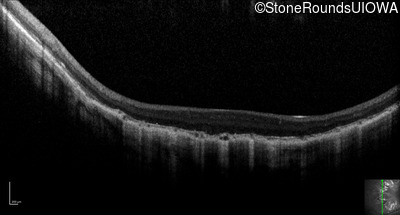

Optical Coherence Tomography - Right - 20/200 -2

Exemplar / OCT Stack

OCT Stack